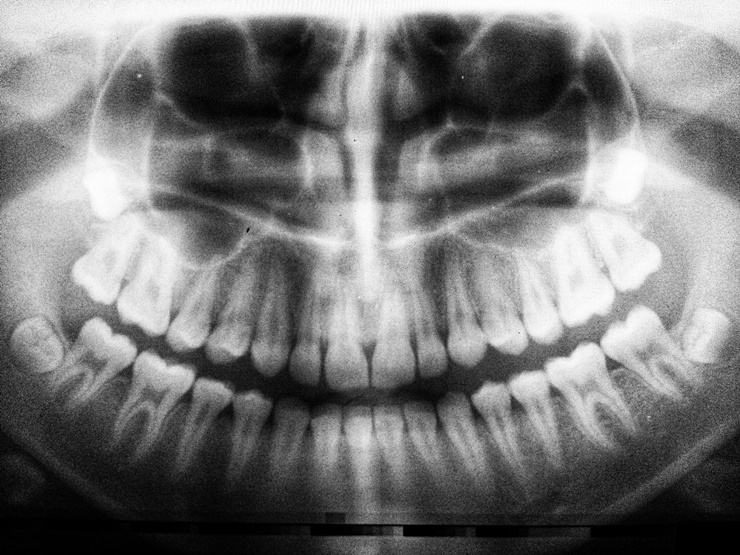

치과 임플란트는 인공 치아를 지지하기 위해 턱뼈에 외과적으로 부착되는 기둥이다. 신경을 되살리지 못하는 경우에, 임플란트를 하게 되는데 뼈 또한 부족하다면 임플란트 인공뼈 이식 과정을 진행하게 된다. 치과 임플란트 경우 성공률이 높지만 일부 사람들은 임플란트 실패를 경험하기도 한다.

임플란트 인공뼈 이식 후, 약 5~10%가 시술 직후 또는 수개월 또는 수년 후에 실패하는 것으로 밝혀졌다. 임플란트 수술 및 인공뼈 이식 전에 알아야할 6가지 사항에 대해서 알아보도록 하자.

3. 턱뼈 부족

성공적인 시술은 임플란트를 지지하기 위한 턱뼈가 중요하다. 뼈가 충분하지 않는 경우 인공뼈를 이식이 가능하다. 그러나, 골다공증으로 골 손실이 발생하는 경우도 있는데, 해당 상태는 골밀도가 감소할 때 발생한다.

뼈가 약해지고 골절 위험이 증가하며, 심한 잇몸 질환의 경우 입안의 뼈를 악화시키는 경우도 대부분이다.